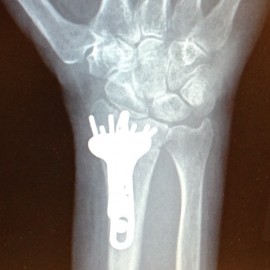

Sounds ominous, doesn’t it? Distal Radius Fracture and Repair. In the case of this blog post, it just means that I broke my wrist, and then had it put back together with hardware that I’ll wear for the rest of